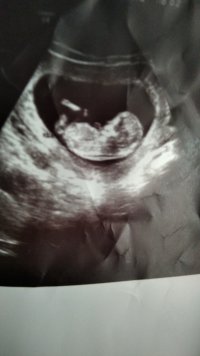

12 haftalık ultrasyon görüntüsune yorum yaparmisiniz

Ekli dosyalar

• IMG_20220111_193521.jpg

IMG_20220111_193521.jpg

3,1 MB · Görüntüleme: 261

Selamlar hayatım. Öncelikle sağ salim kucağınıza almanızi diliyorum. İlgili resim incelendi ama tam net bir şey söylemek mümkün görünmüyor. Elinizde başka resim var ise yükler misiniz ? Bir de nub teorisine göre cinsiyet tahmininde bulunmak isteriz. Bu konumuzu inceleyip resmi nasıl istediğimize lütfen bakınız.